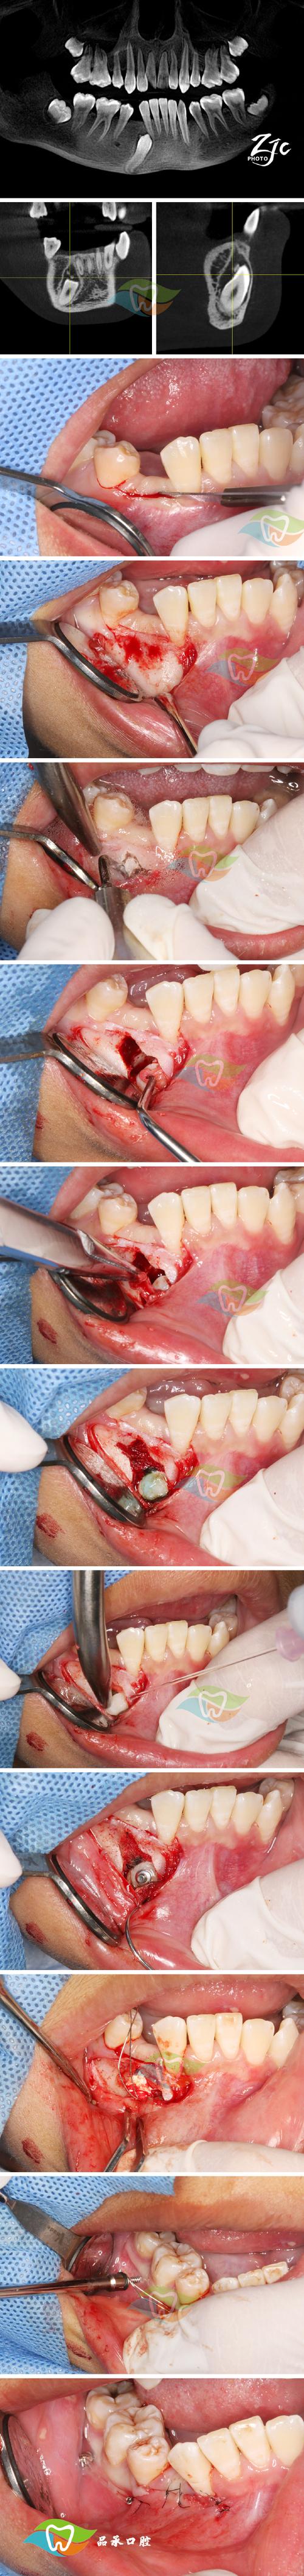

(图片来源网络,侵删)- 原因:

- 生理改建: 牙齿移动过程中,受压侧牙槽骨吸收,牵引侧骨新生,如果改建不协调或骨量不足,可能导致整体骨高度降低。

- 炎症因素: 牙周炎导致牙槽骨吸收。

- 拔牙病例: 拔牙窝区域骨量可能不足,移动牙齿时可能导致骨量进一步减少。

- 施力过大或不当: 可能导致骨组织过度吸收。